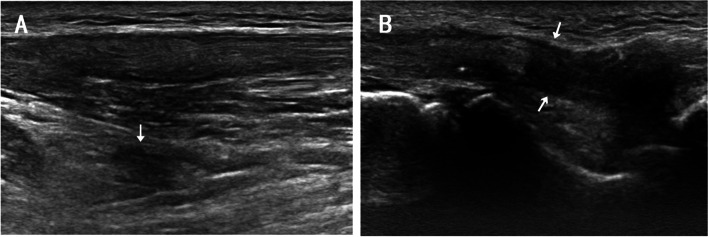

On the ultrasound image, extensor tendon interruption and surrounding edema was detected in the fourth and fifth fingers of the right hand (Fig. 3). On MRI T2-weighted image, a discontinuous high signal in the tendons of the fourth and fifth fingers and edema in the surrounding tissue were detected (Fig. 4). Both MRI and ultrasound results suggested tendon rupture of the right fourth and fifth fingers with remarkable inflammation in the tendons and surrounding tissue.

Fig. 3.

In ultrasonic images, extensor tendon of right ring and little finger was shown ruptured surrounding tissue edema, the proximal end (A) and the distal end (B) were indicated with white arrow